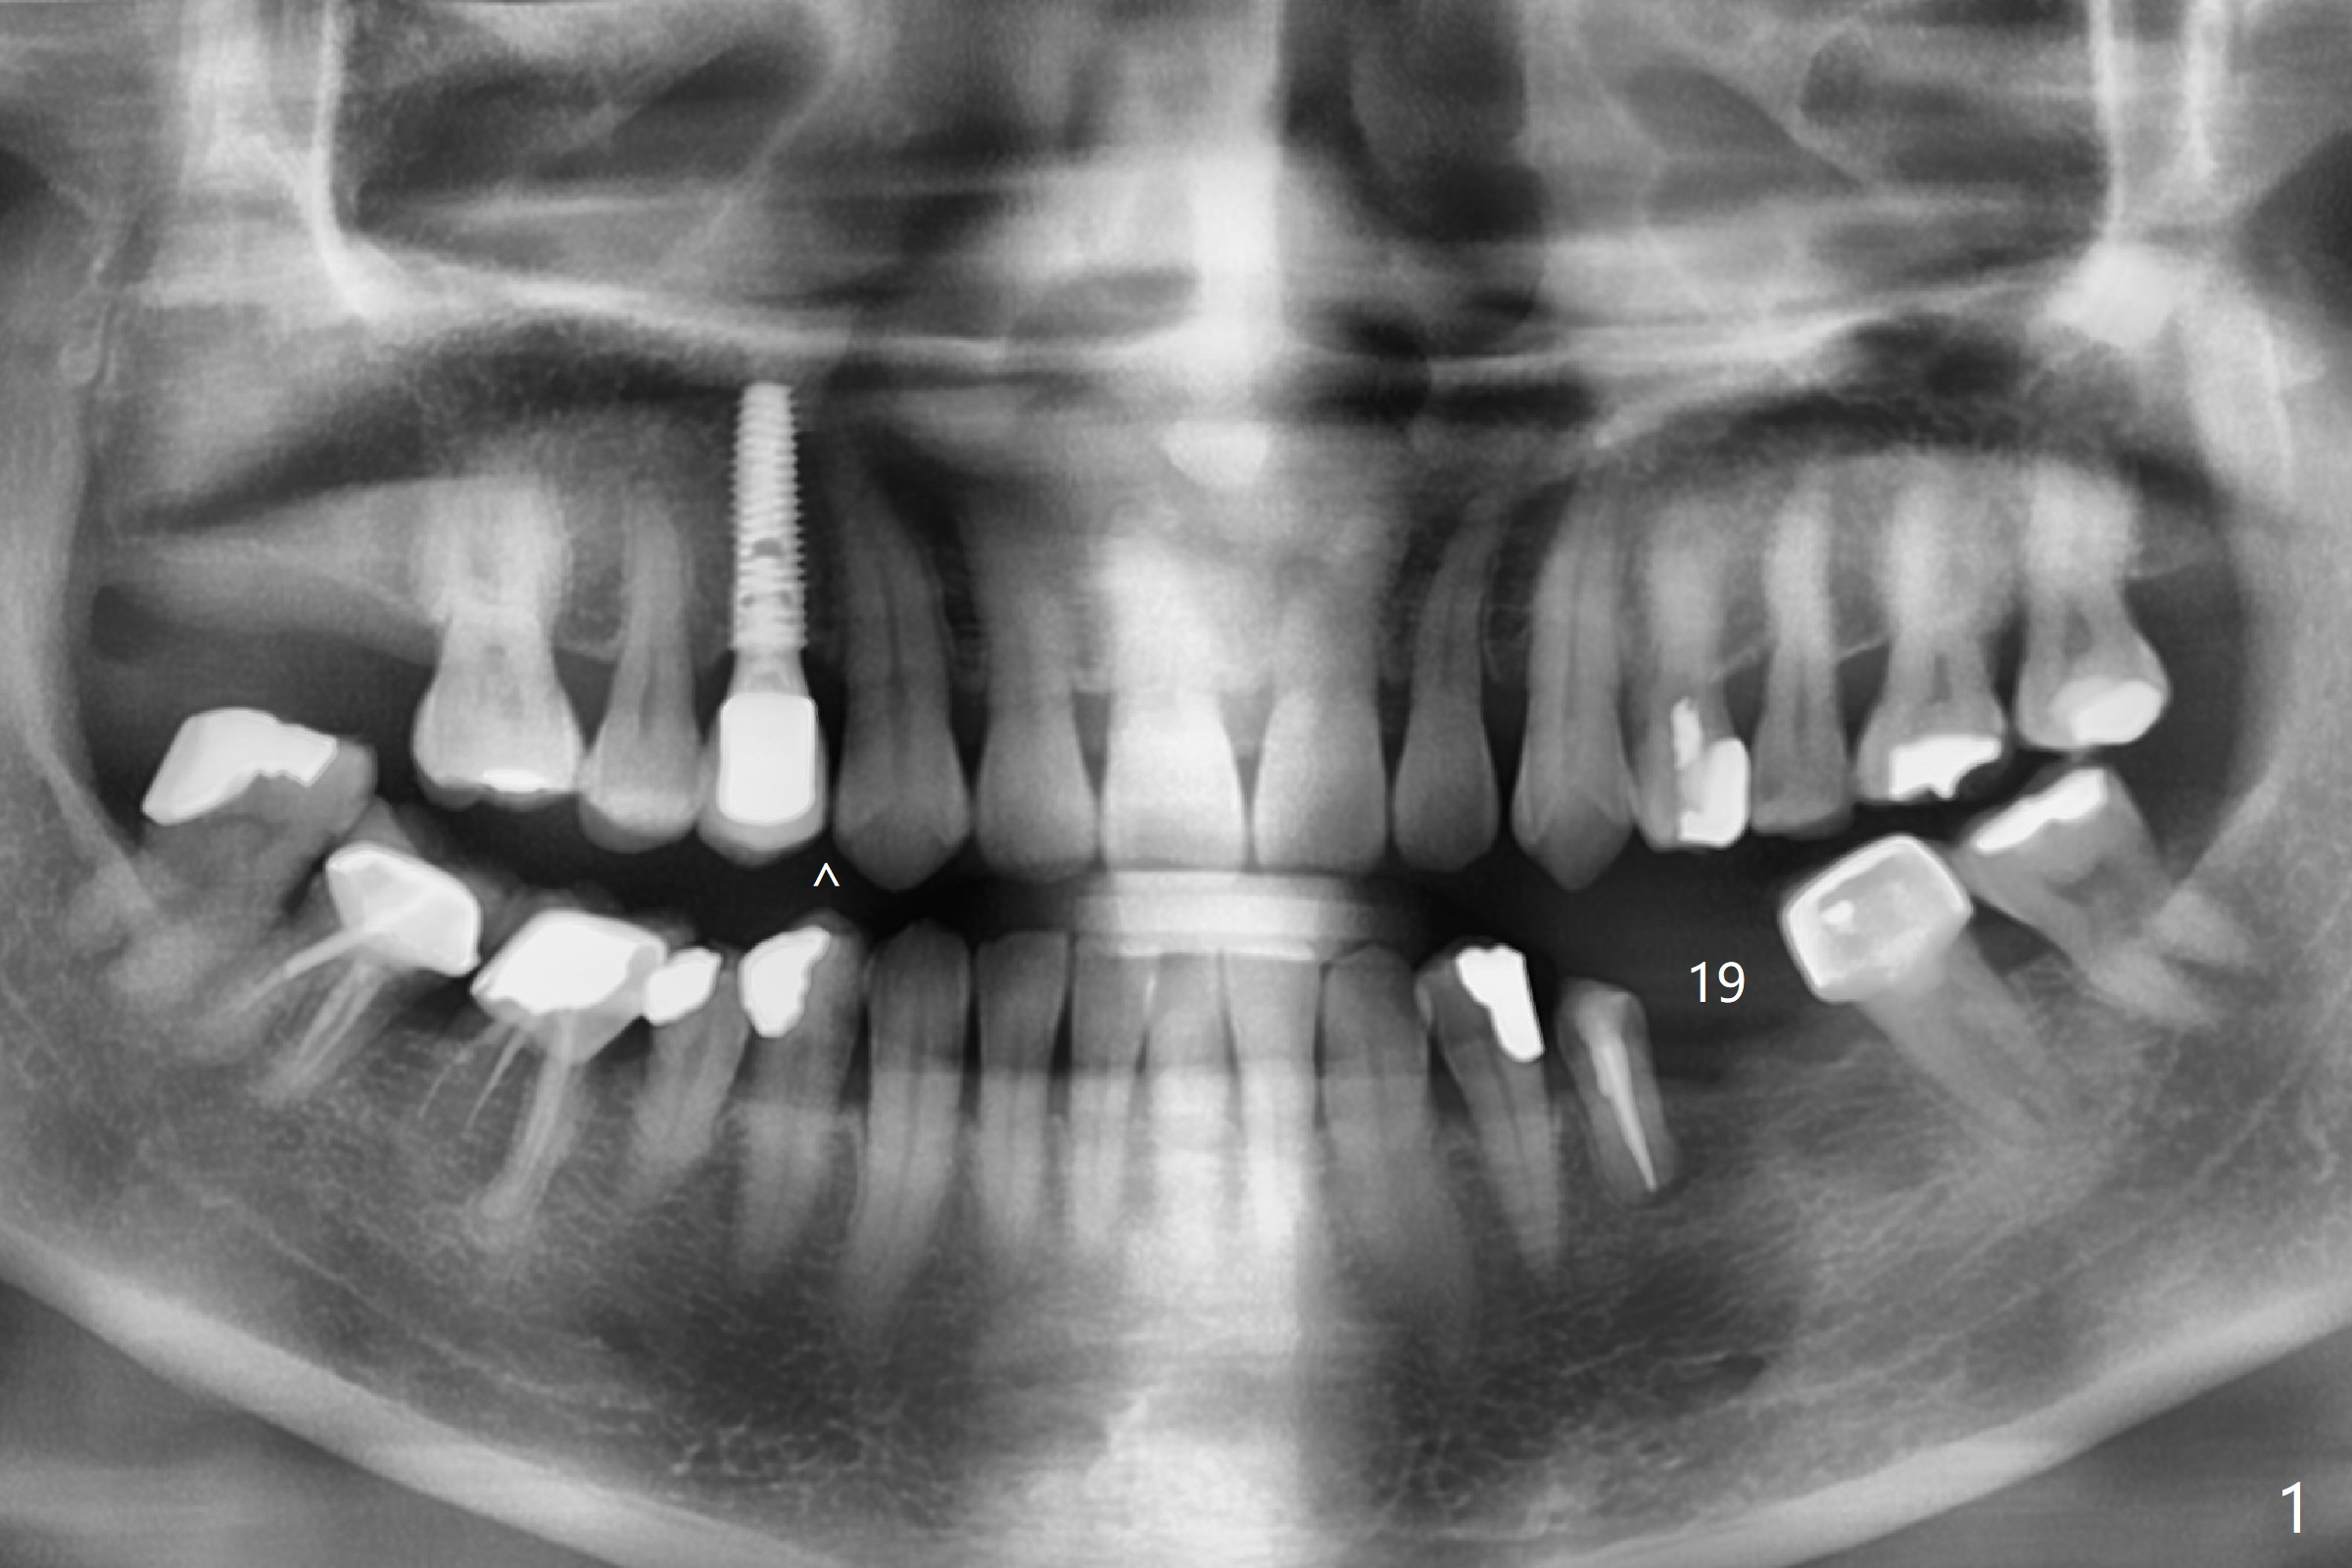

A 52-year-old woman requests an implant at #19 (Fig.1). Her other 2 concerns are the diastema between #5 implant crown and the tooth #6 (Fig.1 (^),2) and whether the tooth #20 is stable enough for crown after sectioning #18-20 FPD and RCT (Fig.1,3 (disto(*)-buccal (B) bone loss)). The ridge at #19 seems to be narrow; a 4x10 mm IS implant appears to be appropriate for the site (Fig.4). Since Magicore has a narrow core and aggressive fins, a 4.0 or 4.5x9(3) mm implant is apparently a good fit. After osteotomy, remove guide, use perio probe to determine crest level and place Magicore